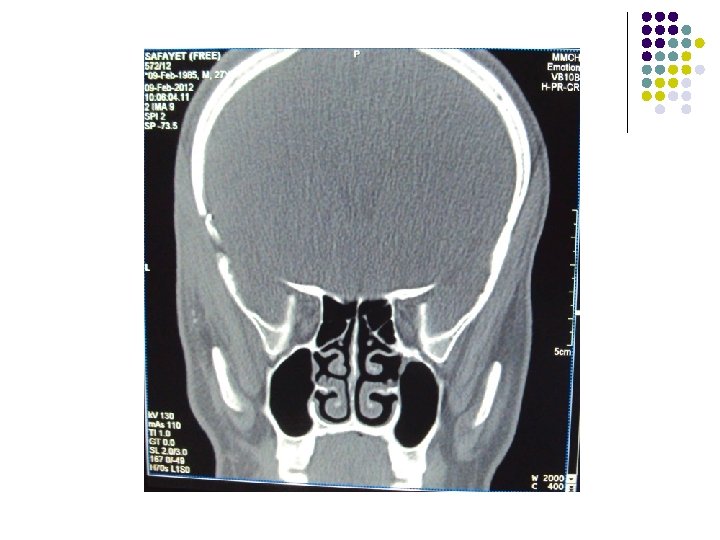

CT Scan of Brain

Clinical Diagnosis Retrobulbar solid tumour on left orbit